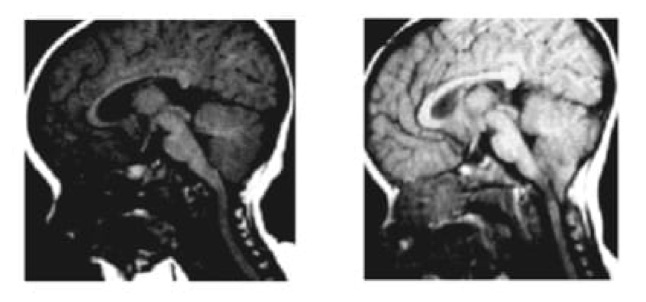

Figure 2.- Résonance magnétique (IRM) d’un patient à 8 et 20 mois, dans laquelle on peut observer un DAC apparu entre les deux IRM. Huang P. « Aquired » Chiari I malformation. J. Neurosurg 1994. Indiquant qu’en plus d’un élément génétique et héréditaire, il existe un facteur acquis.